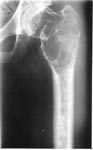

1.Остеобластокастома верхней трети бедра (возраст 24 года)

2.Резекция проксимального отдела бедра с остеомией в нижней трети в аппарате Илизарова

3.На этапе замещения

4.Артродез тазобедренного сустава с доудлинением бедра

5.Результат лечения